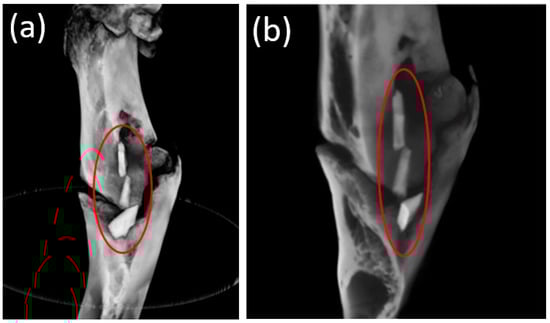

3.4. Cone Beam Computed Tomography

3.5. Micro-CT